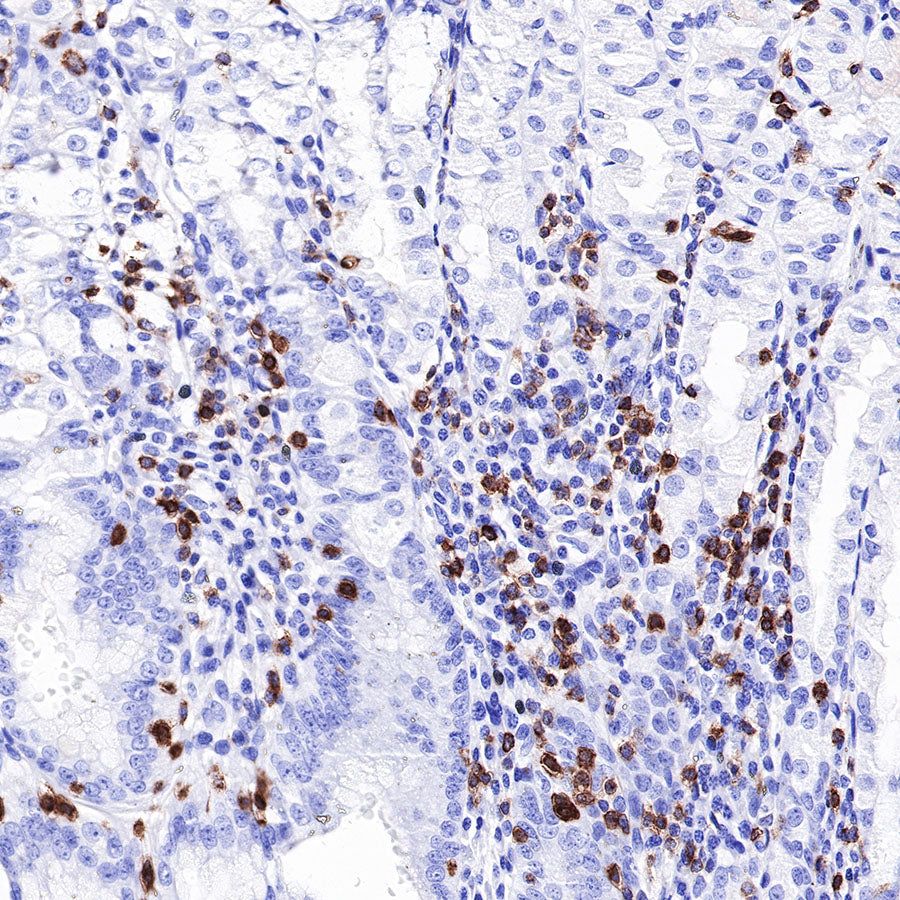

Immunohistochemistry